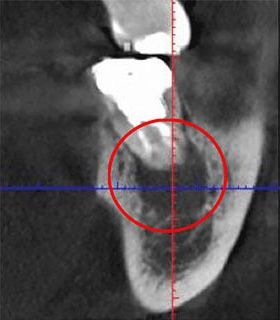

通常は「2次元」で撮影するレントゲンを使用して診断を行いますが、当院では「3次元」での撮影が可能なCTを用いてより詳細な診断を行います。

2次元と3次元では「見える範囲」が異なります。

下の画像は他の治療のケースですが、同じ部位を2次元レントゲン(左)、3次元のCT(右)で撮影したものです。

丸がついている部分が問題の生じている部分で、3次元ではしっかり黒い影が見えますが、2次元ではそれが確認できません。

簡単にまとめると、2次元レントゲンだけでは「問題が見落とされる」可能性があるということです。

歯科医療では、「見える」「見えない」が大きな違いを生みます。

当院では、しっかりとした視野を提供する3次元のCT装置を使って診断を行っています。

主訴 | 親知らずを抜きたい |

|---|---|

治療期間 | 1週間 |

治療費 | 8,000円 |

治療内容 | CT撮影、左下8抜歯 |

治療のリスク | 下歯槽神経麻痺、腫脹、疼痛 |